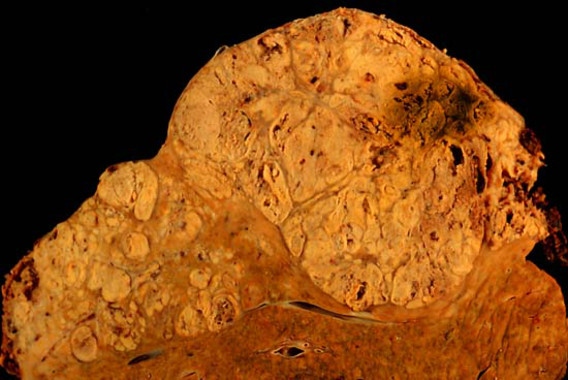

Los niveles más altos de selenio en sangre o de selenoproteína P –la proteína que distribuye el selenio del hígado en todo el cuerpo– se asocian con un menor riesgo de desarrollar cáncer de hígado (en particular carcinoma hepatocelular). Así lo revela un nuevo estudio, publicado recientemente en The American Journal of Clinical Nutrition.

Los resultados, que se mantienen incluso si se tienen en cuenta los otros factores de riesgo de este cáncer, muestran sin embargo que el nivel de selenio no está asociado con el desarrollo de tumores de la vesícula o del tracto biliar.

En 2012, se estima que ha habido 782.000 nuevos casos de cáncer de hígado en el mundo. Es la segunda causa más común de muerte por cáncer, siendo responsable de casi 746.000 fallecimientos en el mismo años (el 9,1% de todas las muertes relacionadas con cáncer ese año).

"La incidencia de cáncer de hígado está aumentando en los países desarrollados. El problema es que a menudo son diagnosticados en fases avanzadas, lo que limita las opciones de tratamiento", concluye Mazda Jenab, experto del IARC y uno de los autores del estudio. "Se necesita más investigación sobre los factores modificables de estos tipos de cáncer y estrategias de prevención eficaces".